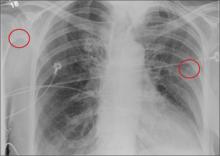

The radiograph shows the lungs overall to be clear. There are some slight increased markings, perhaps suggestive of mild congestion, but no infiltrate or consolidation.

Of note is a small nodule within the middle portion of the left upper lobe that requires monitoring and further workup. Also, although it is incompletely imaged, there appears to be a fracture of the right humeral neck.

Additional imaging confirmed the fracture. Orthopedic consultation was obtained.